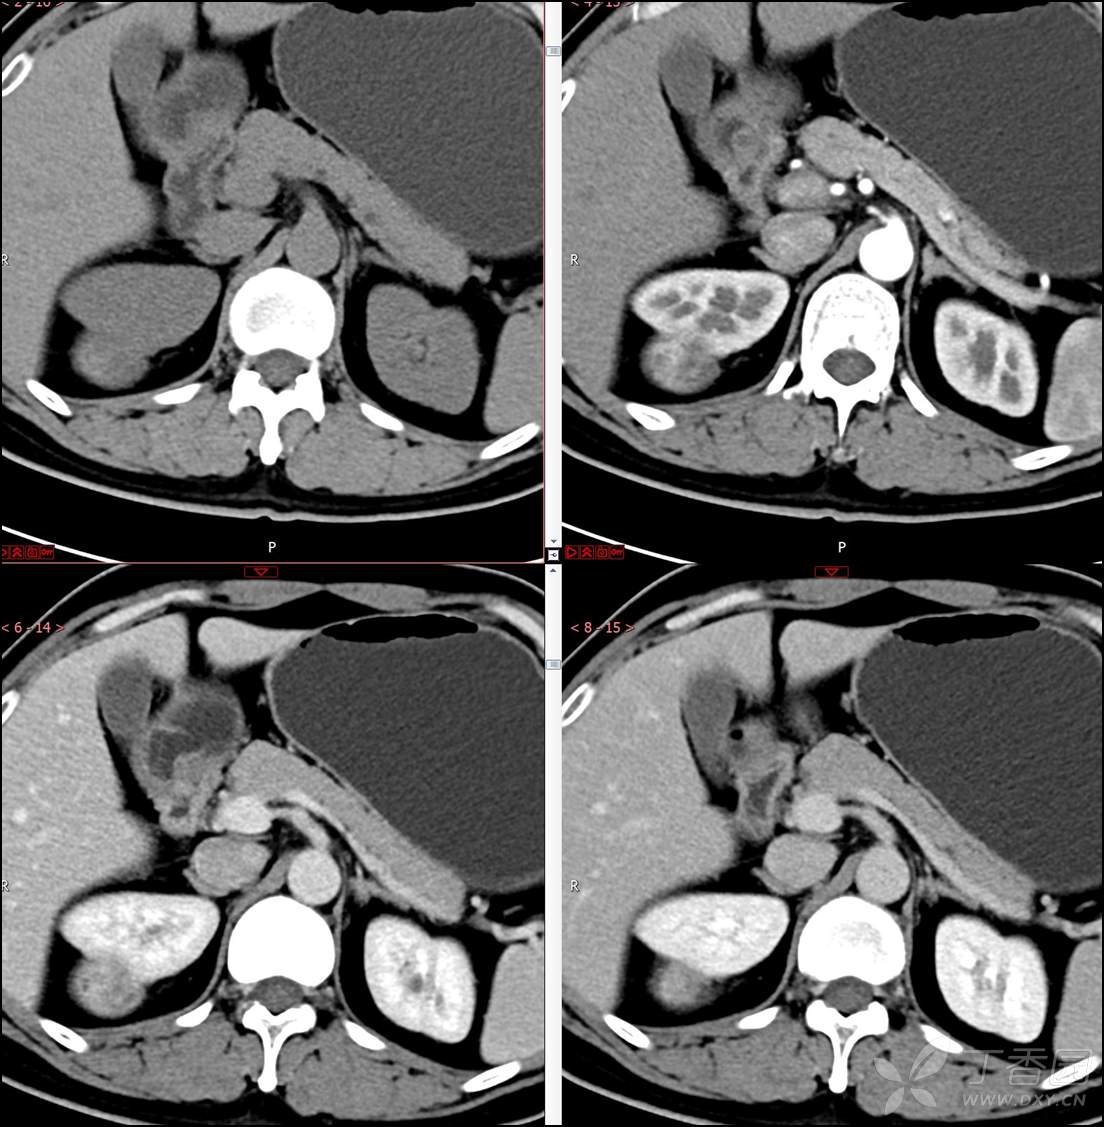

【影诊笔记518】中年男性,查体发现肾脏占位~『回复即可显示答案』

患者年龄:40岁

主诉:查体发现右肾肿物2月余

简要病史:患者2月余前于我院行健康查体,胸部(肺)CT平扫示:右肺中叶结节并右侧阻塞性肺炎;左肺上叶小结节;右肾占位。自诉无腰背部疼痛不适,无尿频、尿急、尿痛,无肉眼血尿,无恶心呕吐,无心悸、胸闷,无发热、寒战等不适,建议进一步检查。现患者为求进一步诊治于为我院就诊,建议手术治疗,门诊遂以“肾肿物(右)”收入院。患者自发病以来神志清,精神可,饮食可,睡眠欠佳,大便正常,体重近期无明显增减。